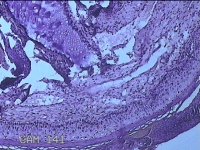

宫颈赘生物

性别

女

年龄

37岁

临床诊断

早期人工流产;宫颈炎性疾病

一般病史

宫颈有1赘生物。

标本名称

大体所见

灰白暗红色肿物1.3x0.8x0.2cm一个,表面糜烂。